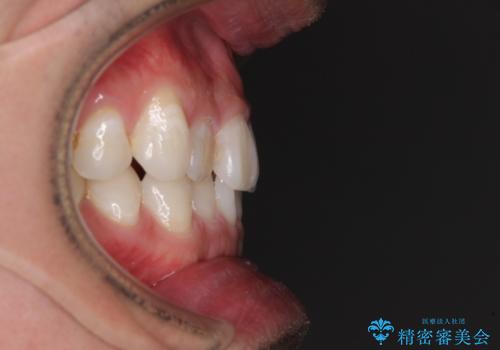

- 上下前歯の叢生を気にして来院された患者様です。

費用を抑え、期間もあまりかけずに治療をしたいとのことで、インビザライン・ライトを用いて矯正治療を行うこととしました。